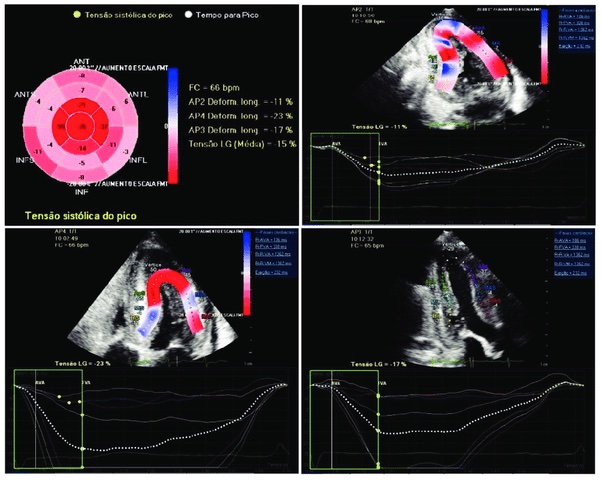

Ecocardiografia speckel-tracking

L’ecocardiografia speckle tracking (STE) è una metodica di analisi ecocardiografica che analizza quantitativamente la funzione globale e regionale del miocardio ventricolare e atriale. Valutando lo spostamento degli speckle che formano l’immagine ecocardiografica durante un intero ciclo cardiaco, è possibile ottenere la misurazione di vari parametri di deformazione miocardica, consentendo così una valutazione oggettiva e quantitativa dell’ispessimento, dell’accorciamento e della rotazione del muscolo cardiaco. Negli ultimi anni, numerosi studi hanno mostrato che la metodica ha ottima fattibilità, riproducibilità e accuratezza diagnostica ed è pertanto applicabile in numerosi contesti clinici.